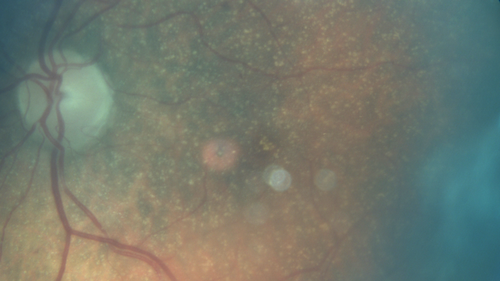

Unusual Intraretinal Deposits

71 year old diabetic man on dialysis with 20/20 vision and intraretinal deposits. Recent 150 lb weight loss, on dialysis, see album properties for full history